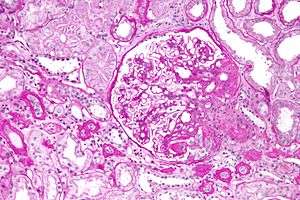

Appearance

The individual components of the name refer to the appearance of the kidney tissue on biopsy: focal—only some of the glomeruli are involved (as opposed to diffuse), segmental—only part of each glomerulus is involved (as opposed to global),[4] glomerulosclerosis—refers to scarring of the glomerulus (a part of the nephron (the functional unit of the kidney)). The glomerulosclerosis is usually indicated by heavy PAS staining and findings of immunoglobulin M (IgM) and C3-convertase (C3) in the sclerotic segment.[5]